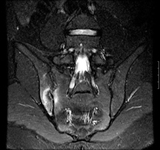

Coronal STIR (მოკლე ტაუ ინვერსიის აღდგენა) მაგნიტურ-რეზონანსული გამოსახულება გვიჩვენებს უნილატერალურ (მარჯვენამხრივ) საკროილიიტს

BMJ 2006;333;581-585. © BMJ Publishing Group Ltd 2009